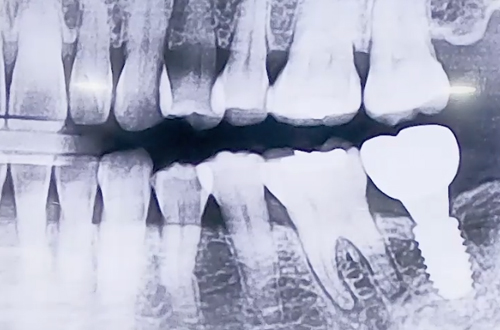

BEFORE

왼쪽 아래 어금니가 음식을 씹을 때마다 통증이 있어

본원을 내원해 주셨던 환자분의 사례입니다.

왼쪽 아래 뒤에서 두번째 큰 어금니의 뿌리 주변으로 잇몸이 약해지면서

염증이 생기고, 치아가 굉장히 많이 흔들리고 있었습니다.

잇몸이 원인이 된 상황이므로 해당 치아를 발치하고 임플란트를 결정하였습니다.